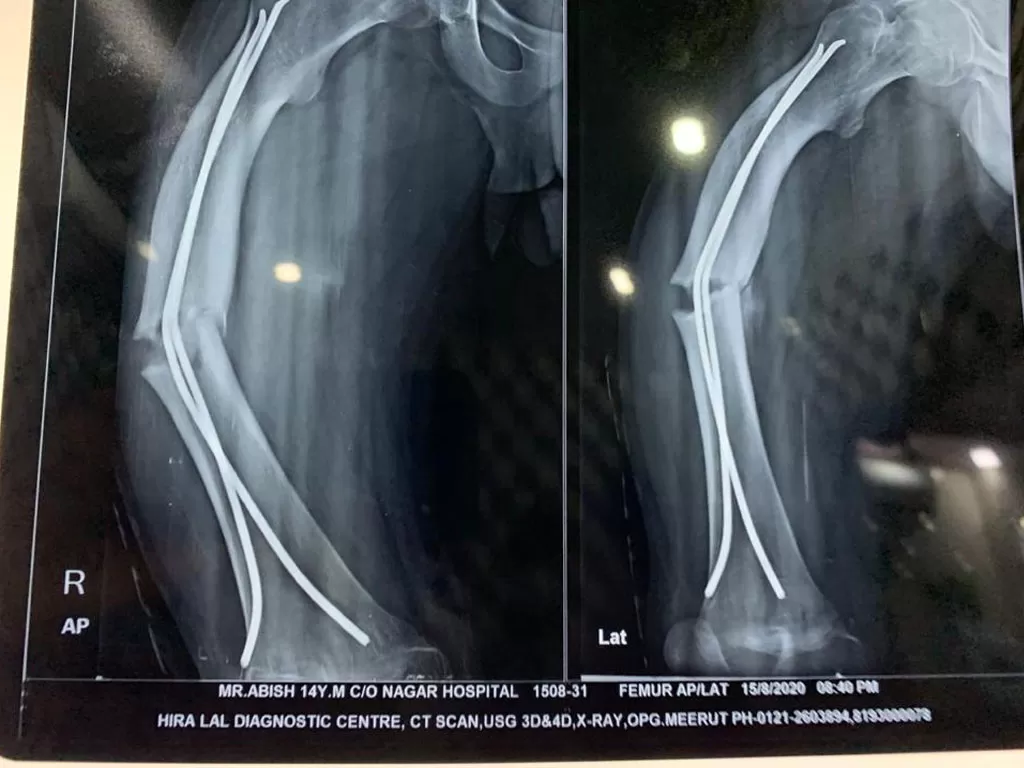

Mr. Abish

Name: Mr. Abish

Date of Operation: 23 Aug 2020

Age: 14 Years